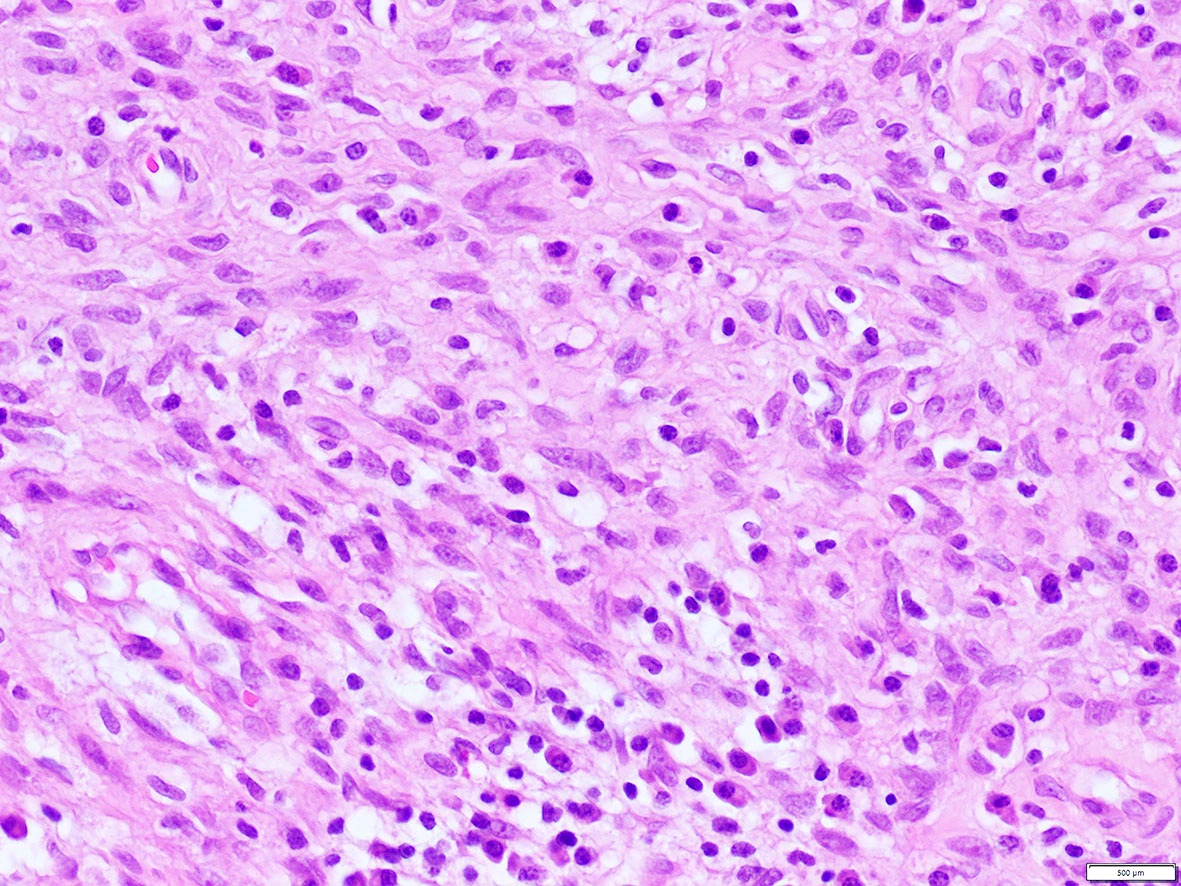

Microscopic (histologic) images

Contributed by A. Cristina Vargas, M.B.B.S., Ph.D., Patricia Guzman, M.D., Fiona Bonar, M.B.B.Ch., Alison Cheah, M.B.B.S. and Martin Jones, M.B.B.S.

What is the expected diagnosis for a uterine spindle cell tumor with this histological appearance? The tumor displayed focal smooth muscle expression, strong ALK overexpression on IHC and an ALK translocation was confirmed by FISH.